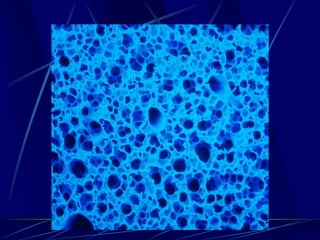

Microstructure

Pulmonary Surfactant

Surfactant

 90% lipids

 10% Proteins

Hydrophilic: SP-A and SP-D

Hydrophobic: SP-B and SP-C

Curr Opin Crit Care 10, 2004: 18-22

Pulmonary Surfactant was

initially

identified as a lipoprotein

complex that reduces

surface tension at the air-

liquid interface of the lung

Lipids

   Levels of total phospholipids decrease

over time with cyclic opening and closing

especially phosphatidylcholine and

phosphatidylglycerol, which are essential

for lowering surface tension at the

alveolar capillary membrane.